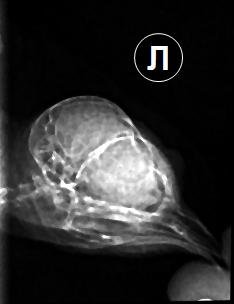

Ирина_2020 Опубликовано 6 февраля, 2023 Автор #71 Опубликовано 6 февраля, 2023 В декабре стрижик снова заболел - плохое самочувствие и над глазом вскочила твердая шишка. Решили, не дожидаясь приема и результатов посева снова давать Панцеф (Супракс), к которому по прошлому посеву была чувствительность, бактериофаг клибсиелл и ирунин. Новый посев показал правильность этого решения, месяц пропили курс и стриж, кажется, выздоровел. За шишкой стали наблюдать - ее размер не менялся. Дней восемь назад ему снова стало становиться хуже, взяли мазок из горла на посев и снова стали давать Панцеф. 2 февраля на приеме у врача отдали мазок, сделали рентген, на котором видно, что глазные и носовые каналы эта гнойная пробка не задевает, но больше покажет только КТ. Иссечь и вычистить, по словам врача - опасно, слишком близко к мозгу и много мелких сосудов. Сейчас 5 дней пьем панцеф, бактериофаг, ирунин, гепатовет (для защиты печени), линекс и мелоксидил. Глаза тоже воспалены и с трудом открываются - их промываем гиланом и тобрексом. Позавчера вид стрижа был очень больной, вчера немного улучшилось состояние, а сегодня целый день он вялый, каким никогда раньше не был. Обычно спит в одном уголке спальной коробки, а сегодня постоянно перемещается по ней, как будто ищет удобное место... Может, а/б не работает и заменить его на имипенем или амикацин, к которым в прошлом посеве тоже была чувствительность?